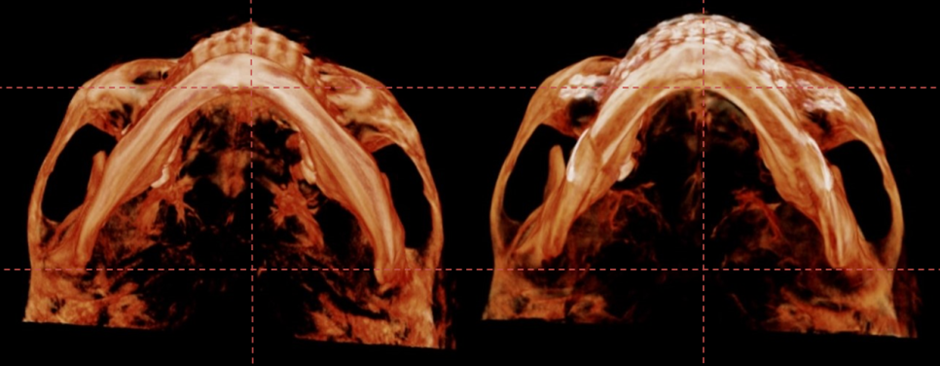

턱끝을 2단으로 절골하여 가운데 뼈를 제거하는 샌드위치 테크닉으로

턱끝의 길이를 5mm 줄이면서 앞으로 6mm 전진 시켰고,

단차가 생긴 뒷부분의 하악 하연을 매끄럽게 잘라낸 후 잘 다듬어서

앞턱 전체를 감싸면서 체부볼륨이 증가 될 수 있도록 이식하였습니다.

수술 3개월이 경과한 시점에 촬영한 CT입니다.

이식한 뼈는 자연스럽게 리모델링 되면서

거의 흡수 없이 잘 생착 된 상태로 회복하였습니다.